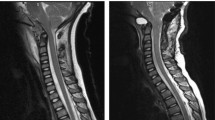

An MRI scan (signa 1.5 T) of the brain and whole spinal cord was undertaken within 24 h of the injury, which failed to show any abnormalities. MRI was again repeated 3 weeks after the injury. This showed an area of abnormal high signal within the posterior aspect of the cord from C3 level down to C4/5 disc space (Figure 1). The MRI brain revealed an area of high signal lying high within the left cerebral hemisphere just supero-lateral to the left ventricle (Figure 2).

(a) The image attached depicts a saggital T2, STIR sequence MRI scan, taken 3 weeks after the accident (no axial views were taken at this time) showed an area of abnormally high signal within the posterior aspect of the spinal cord from C3 to C4–C5 disc space. (b) This image depicts a saggital T2 weighted sequence MRI scan, taken 7 weeks after the accident, there is again a zone of faint increased signal within the posterior aspect of the cord just extending from C3 to C5, but principally being present at the level of C4. (c) This is an axial T2 weighted sequence MRI scan again 7 weeks after the accident where the high signal appears to be located with two almost punctuate-like foci in the posterior aspect of the cord at the level of C4